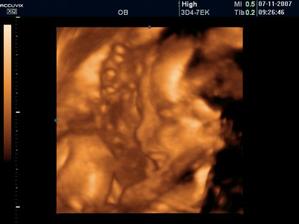

Chrobáčik a my